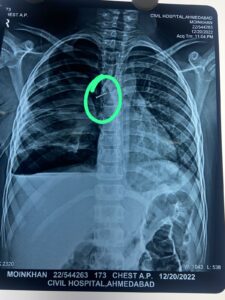

અમદાવાદ સિવિલ હોસ્પિટલમાં 18 મી ડિસેમ્બરે પહોંચ્યા ત્યારે તેનું એક્સ-રે અને સી.ટી. સ્કેન કરવામાં આવ્યું. આ રીપોર્ટમાં સોફ્ટ બોર્ડ પીન શ્વાસનળીમાં ફસાયેલી હોવાનું જણાઇ આવ્યું. જેની સર્જરી કરવી અતિઆવશ્યક હતી.

બાળરોગ સર્જરી વિભાગના વડા અને સિવિલ હોસ્પિટલ સુપ્રીટેન્ડન્ટ ડૉ. રાકેશ જોષી અને ડૉ. અનીઝ રતાણી તેમજ એન્સેશિયા વિભાગમાંથી ડૉ. અનીષા ચોક્સી અને તેમની ટીમે 21મી ડિસેમ્બરે મોહિનની સર્જરી કરવાનો નિર્ણય કર્યો. બ્રોન્કોસ્કોપિ સર્જરી દ્વારા શ્વાસનળીમાં ફસાયેલી પીન બહાર કાઢવાના પ્રયત્નો હાથ ધરવામાં આવ્યા.

આ સર્જરી દરમિયાન જોવા મળ્યું કે પીન જમણા ફેફસામાં ભરાઇ જતા ફેફસામાં કાણું પડી ગયું હતુ.એક કલાકની ભારે જહેમત બાદ ખૂબ જ તકેદારીપૂર્ણ સર્જરી હાથ ધરીને પીનને સાવચેતીપૂર્ણ બહાર કાઢવામાં તબીબોને અંતે સફળતા મળી.